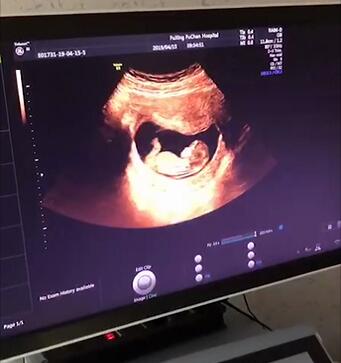

三、四维大排畸

做这项检查时候可以多角度观察到宝宝的发育情况,比如胎儿的器官发育,手脚脊柱发育是否出现了畸形,当然毕竟医学手段还有一定的局限性,四维彩超也并不是什么畸形都能检查出来,比如胎儿的眼睛听力就无法得知,还有一些先天性的疾病也无法得知。